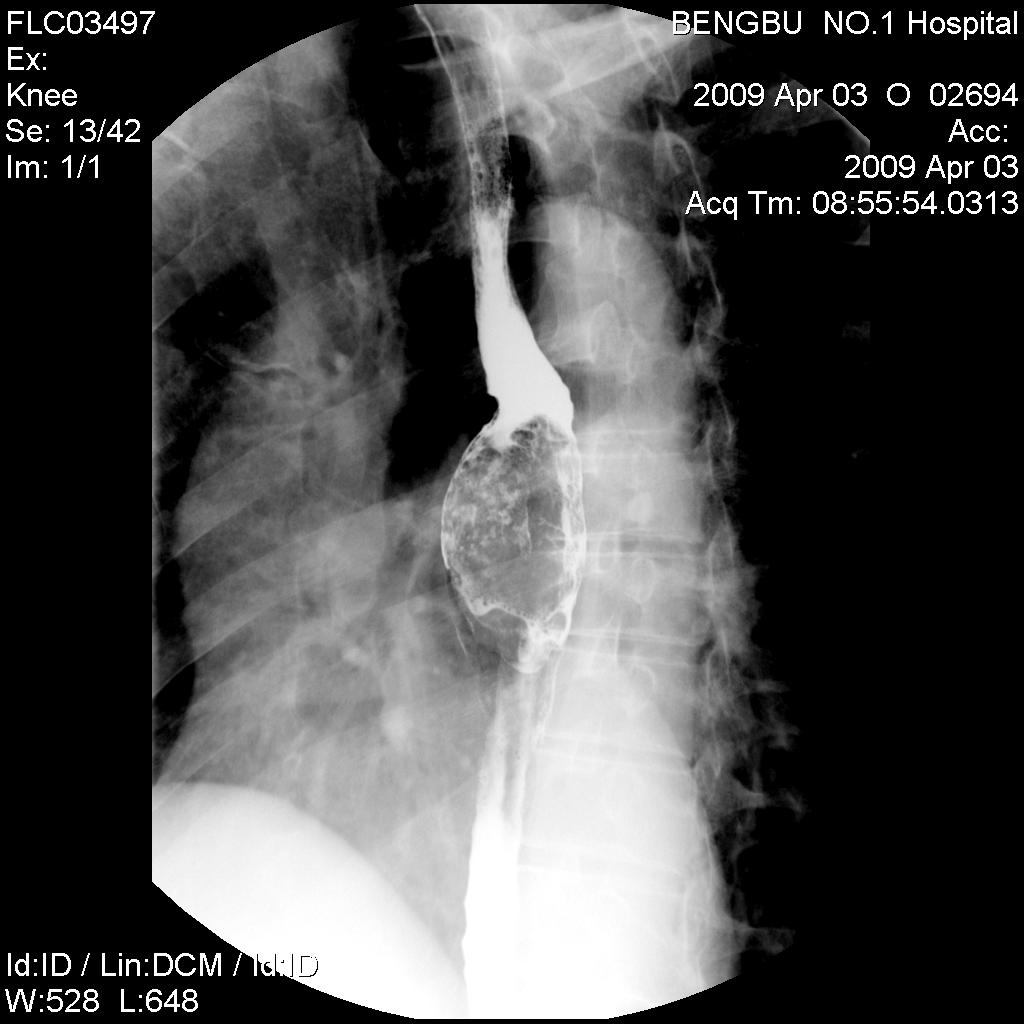

标题: X5565:男,50岁,吞咽阻塞感1月余。 [打印本页]

标题: X5565:男,50岁,吞咽阻塞感1月余。

食管中下段椭圆形充盈缺损,钡剂呈分流尚通畅,粘膜未见明显中断,其上段未扩张。初步考虑食管平滑肌瘤。曾有一病例影像表现类同,结果似为未分化癌。

食管中下段椭圆形充盈缺损,钡剂呈分流尚通畅,粘膜未见明显中断,其上段未扩张。初步考虑食管平滑肌瘤。

食管中下段椭圆形充盈缺损,边缘尚光滑,钡剂呈分流状通过块影,粘膜未见明显中断,管壁未见明显僵硬和缩窄改变。-----平滑肌瘤可能性大。

诊断:食管中下段椭圆形充盈缺损,边缘清晰光滑,肿块表面钡剂涂布征,似见细小龛影,钡剂分流改变,患段官腔扩张度及柔软度尚好,无明显僵硬及狭窄,上段以上食管未见明显扩张及钡剂储留,考虑食管平滑肌瘤,未除外溃疡性食道癌,建议食管镜活检。

肿块呈腔内膨胀性生长,边缘光滑

结果:食道癌。